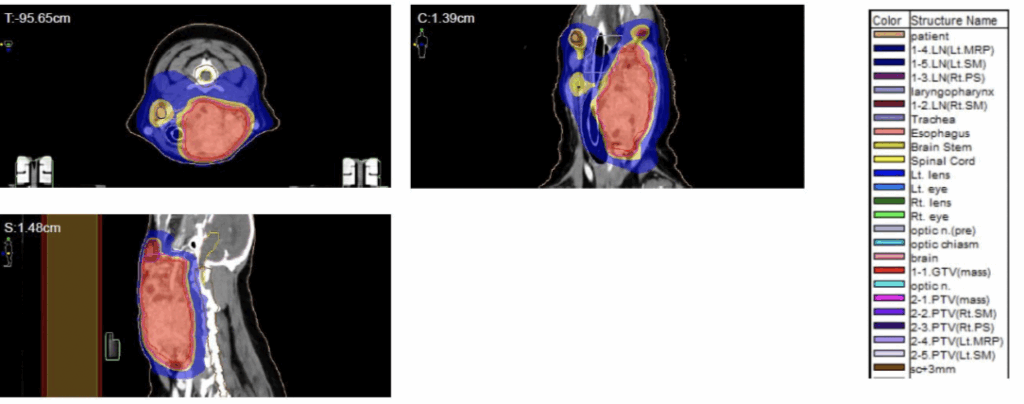

그리고 보호자님의 치료 의지가 강하셨기에 빠른 일자에 방사선치료용 모의CT 촬영을 진행하였고 타원 CT와 비교하였을 때, 아직 변화가 일어나지 않은 상태였습니다.

갑상선암 강아지 환자의 방사선치료용 모의 CT검사 / 출처: 에스동물암센터

환자는 만성 질환 없이 건강하게 지내온 환자로 마취 위험도가 낮아, 보호자님과 상의 후 총 20회 저선량·고분할 방사선치료 프로토콜을 적용하기로 하였습니다.

이번 갑상선 암 방사선치료는 기대 수명 연장을 목표로 진행하였습니다.